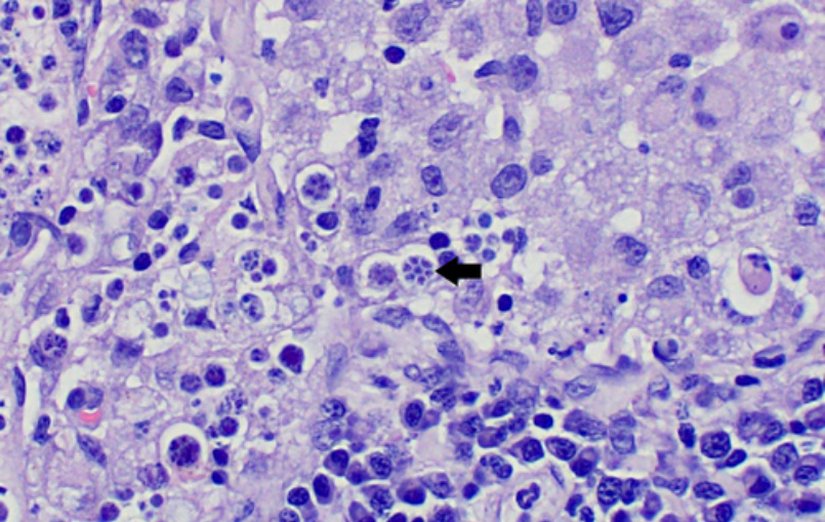

Prototheca, dairesel bir hücre yapısına sahip olup türe ve gelişme evresine göre çapı ve büyüklüğü değişmektedir. Lakin tipik olgun bir Prototheca hücresi 2-30 mikrometre çapa sahip olup ancak ışık mikroskobunda gözlemlenebilen çoğunlukla saydam görünen bir mikroalg genusudur. Mikroskobik muayenesi mutlaka boyama yapılarak gerçekleştirilmelidir.

Prototecha endosporulasyon olarak adlandırılan bir çeşit eşeysiz üreme şekliyle kendi soyunu devam ettirir. Histopatolojik veya sitolojik boyama teknikleri sayesinde bir vejetatif hücre içerisine bulunan birden fazla soyu tespit etmek mümkündür. Bu da mikroskoptaki karakteristik özelliklerinden birisidir.